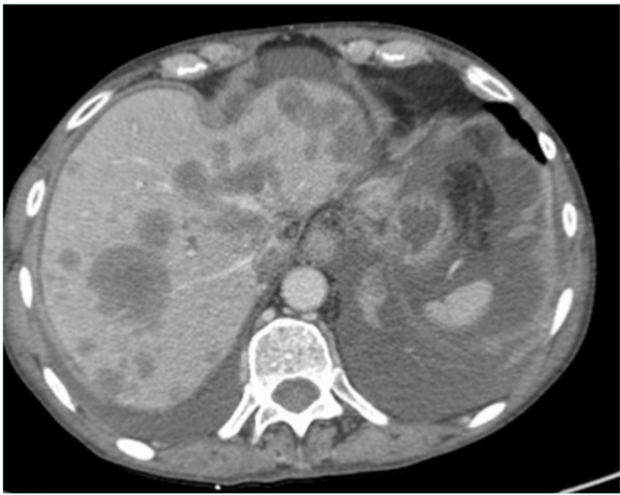

Computed tomography (CT) venography is an easily available and the most commonly used imaging technique as it can be performed through peripheral venous access with injection of 150 mL of iodinated contrast agent with acquisition at 90 and 120 seconds4 (Figures 2 and 3). According to a recent Delphi consensus, it should be the first-line imaging technique.5

Figure 2. Computed tomography (CT) scan in a patient with metastatic liver and ascites with inferior vena cava occlusion.

Both techniques can depict the tumoral and vascular lesion(s). CT angiography and CT venography (or MRV) are mandatory in order to look for tumor vascularization, IVC status (obstruction or occlusion [Figures 2 and 3]) and collateral pathways. According to O’Sullivan, CT venography should be proposed in all cancer patients with lower-limb edema.2